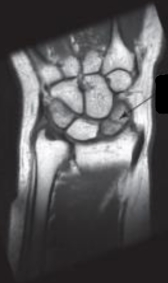

-Refer to the figure. Name the imaging modality and the plane.

A) MRI, coronal plane

B) MRI, sagittal plane

C) CT, coronal plane

D) CT, sagittal plane

-Refer to the figure. The arrow is pointing to a:

A) Tear of the triangular fibrocartilage complex

B) Fracture of the scaphoid

C) Avascular necrosis of the lunate

D) Fracture of the capitate